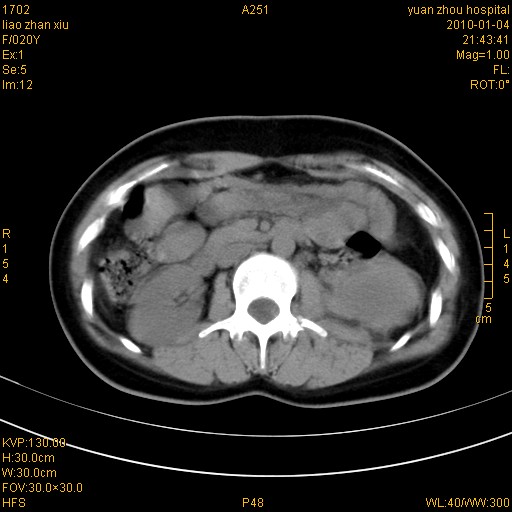

标题: CT23985:F20Y 外伤典型病例 [打印本页]

标题: CT23985:F20Y 外伤典型病例

左肾挫伤,包膜下积血,l3、4左侧横突多发骨折。

2、l3、4左侧横突多发骨折;

气死我了,明明l1、2,为什么都说3、4.

左肾挫伤,包膜下积血,L1、2、3、4左侧横突多发骨折。